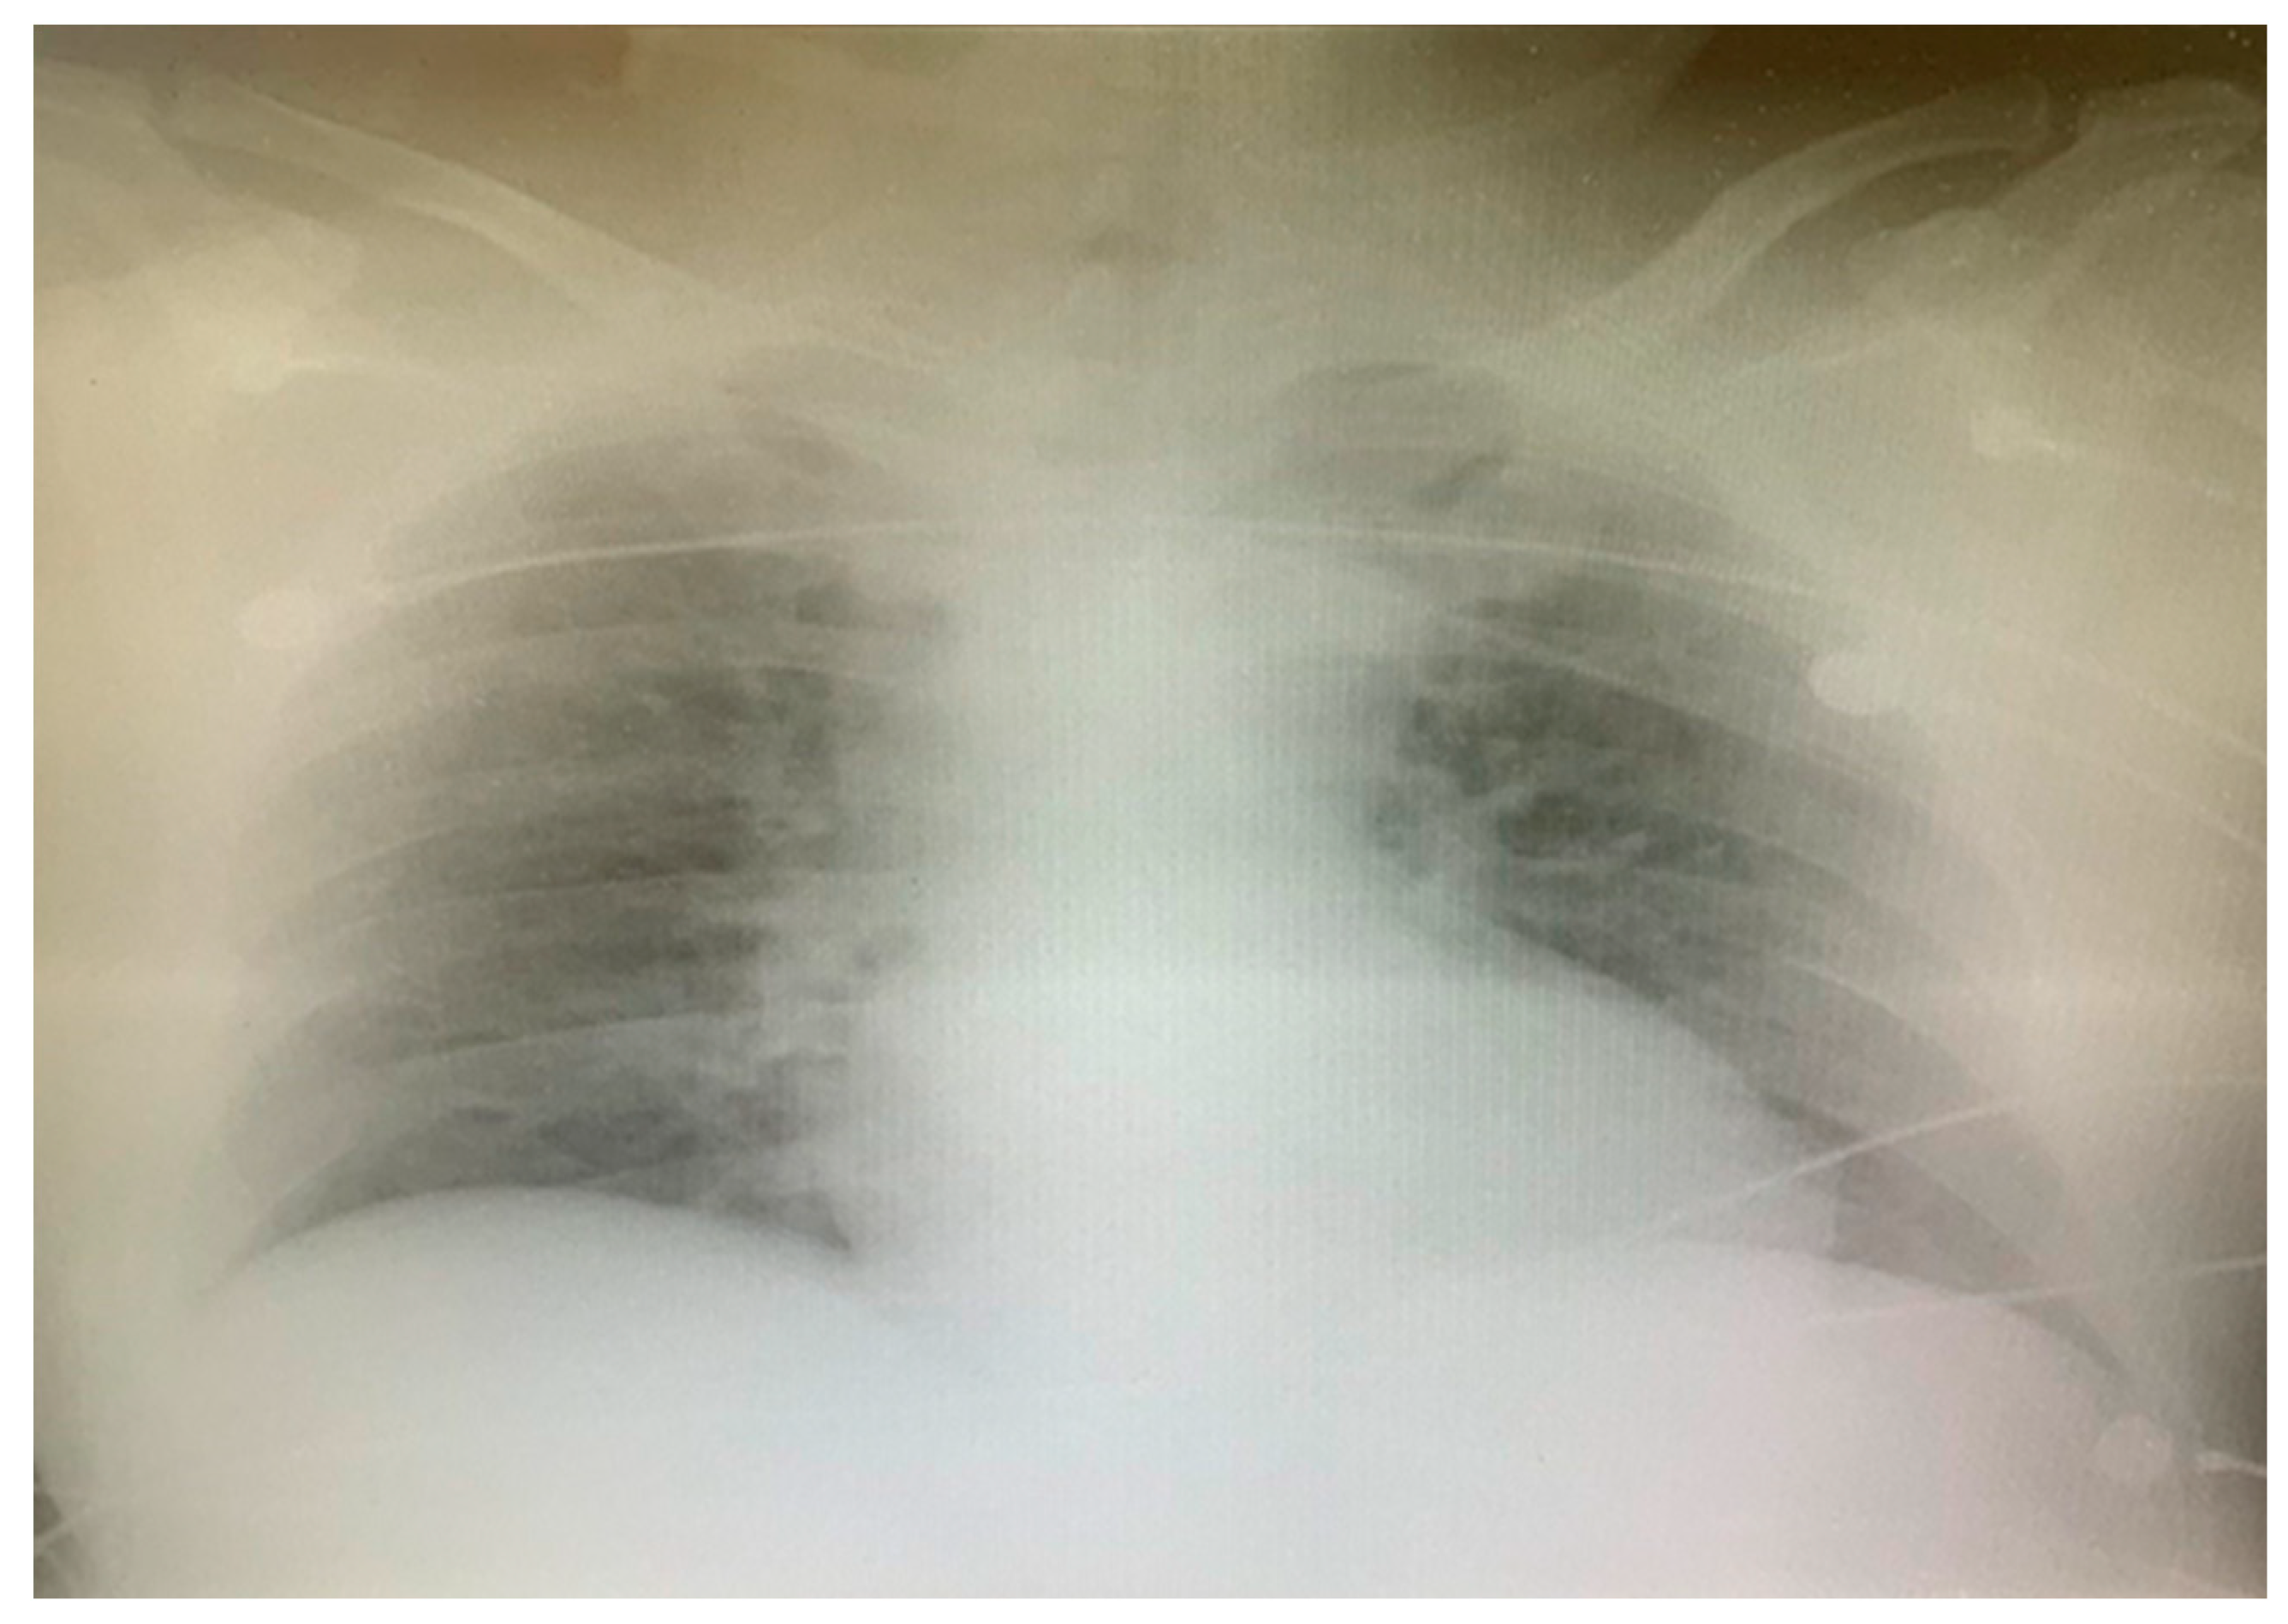

2. Case Report